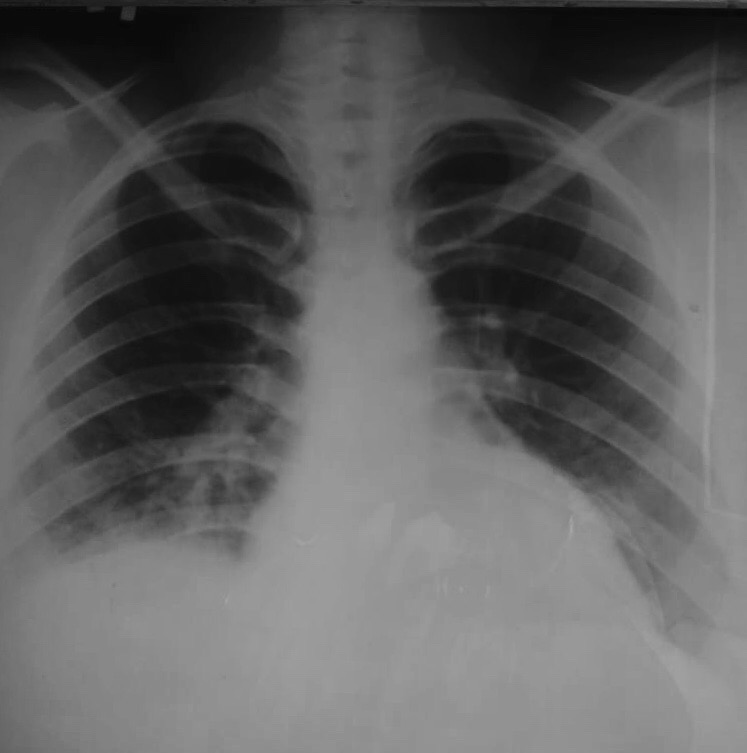

ТЭЛА: высокое стояние купола диафрагмы справа, увеличено правое предсердие

Обсуждалось здесь viewtopic.php?f=24&t=876